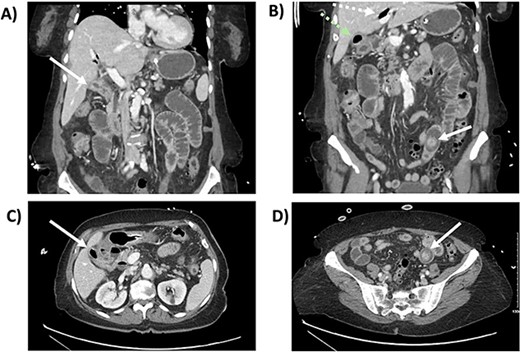

This is the case of an 86-year-old female with an independent baseline functional status and a history of hypertension and prior episodes of medically treated cholecystitis per patient preference. She presented to the Emergency Department at a public major tertiary care hospital for abdominal pain and was found to have a gallstone ileus. A CT scan showed: a gallstone in the jejunum causing a bowel obstruction proximally, pneumobilia, gallbladder wall edema, and pericholecystic fluid (Fig. 1). A nasogastric tube was placed for bowel decompression prior to proceeding for urgent operative exploration.

CT scan from the initial episode of gallstone ileus. A) Coronal CT: cholecystoduodenal fistula, B) Coronal CT: pneumobilia (superior, white dotted arrow) and air-filled gallbladder (inferior, green dotted arrow), impacted gallstone (solid white arrow), C) Axial CT: cholecystoduodenal fistula, D) Axial CT: impacted gallstone.